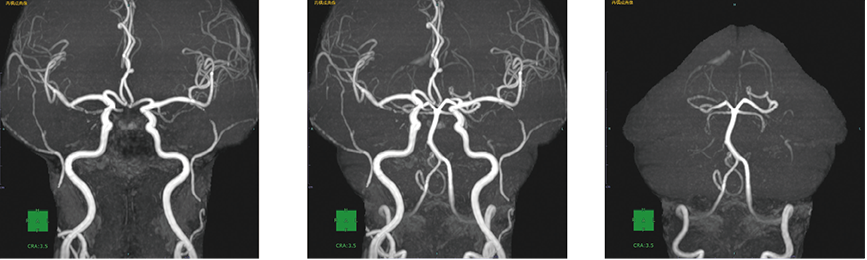

血管観察において不要領域を削除したVR/MIPを表示します。前方循環/後方循環の領域のみに限定した表示も可能です。